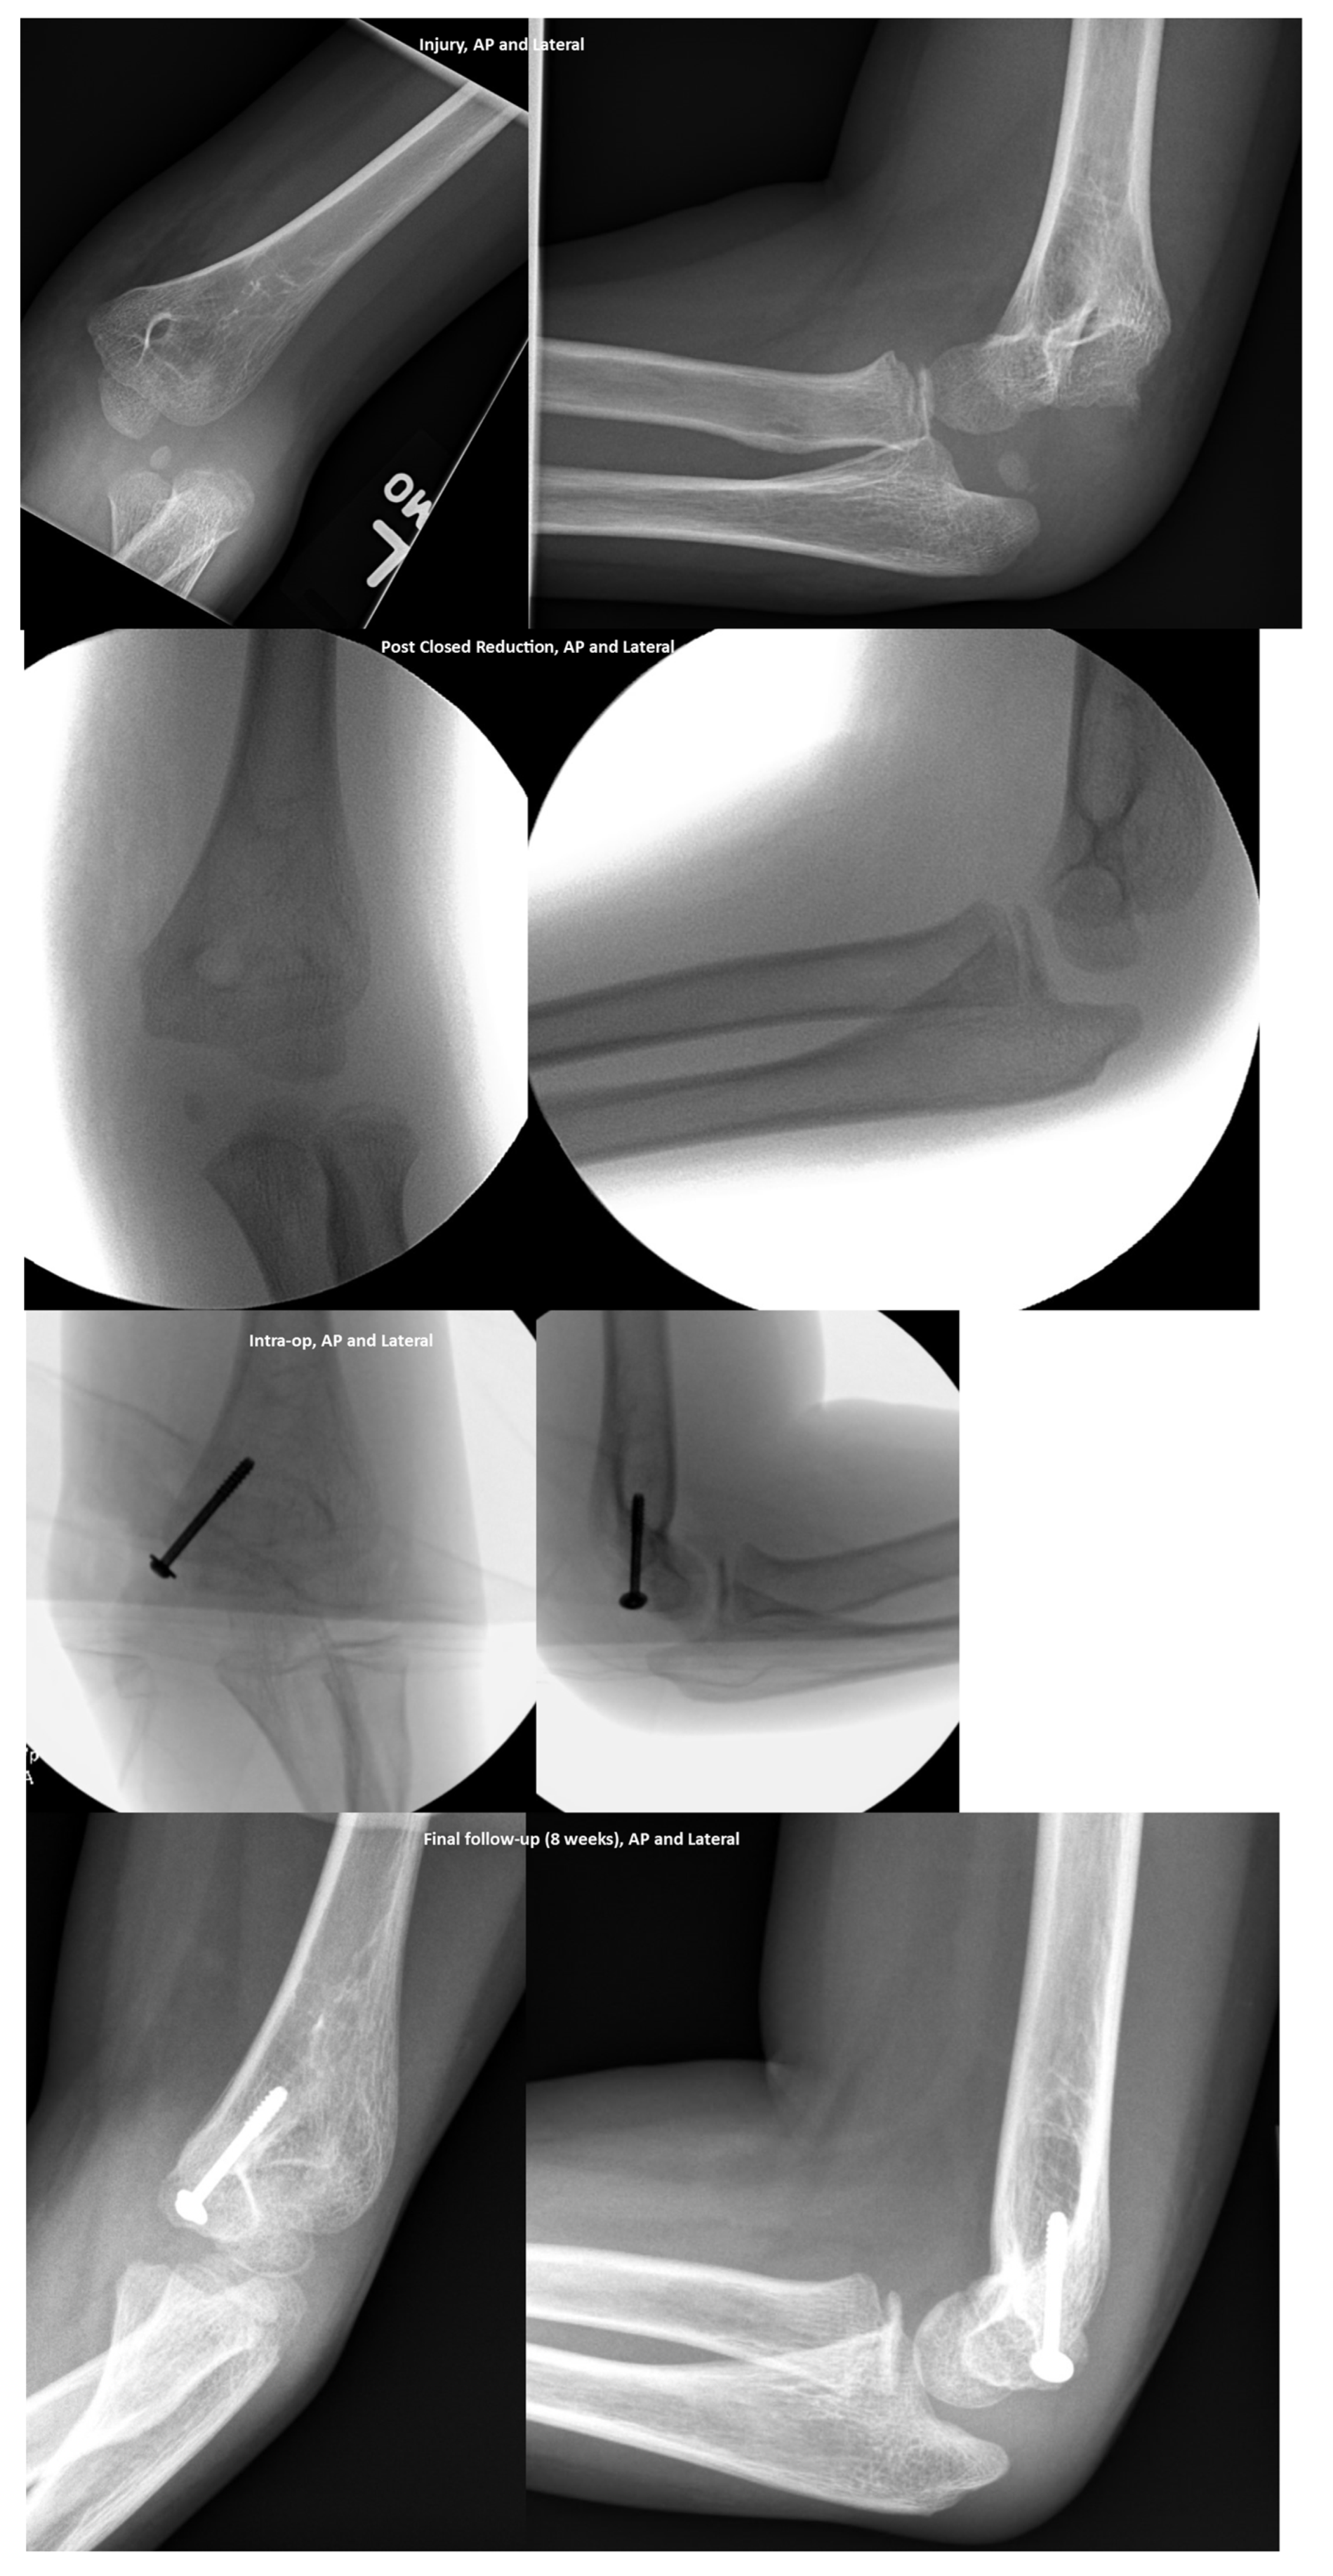

Pediatric Elbow Dislocations and Associated Fractures

3.3. Treatment